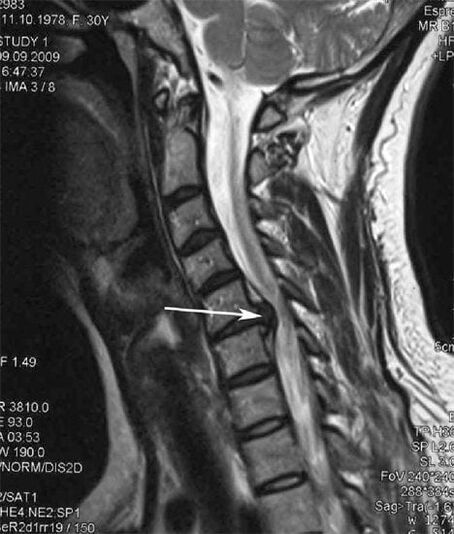

В началните етапи остеохондрозата се открива с помощта на ЯМР. По-късно патологията може да бъде диагностицирана с помощта на радиография. На рентгенографията на шийния отдел на гръбначния стълб се забелязва намаляване на разстоянието между прешлените, патологични промени в фасетните стави и остеофитоза.

| Цервикална остеохондроза | Появата на патологични промени в един или повече гръбначно-двигателни сегменти. Нарушена подвижност на гръбначния стълб, развитие на миофасциални болкови синдроми и прищипване на гръбначните корени | Болка, парестезия и двигателни нарушения в цервикалната област, които се разпространяват в задната част на главата и горните крайници. Откриване на характерни промени в гръбначния стълб при ЯМР и рентгенови снимки (остеофити, намалено разстояние между прешлените, признаци на увреждане на междупрешленните стави) |

Много хора се оплакват, че не могат да обърнат врата си поради силна болка, която се появява след внезапно вдигане на нещо тежко. Това явление показва образуването на дискова херния. Причината за болката в гърба, шията и горния крайник е прищипване на едно от нервните коренчета, излизащи от гръбначния мозък.